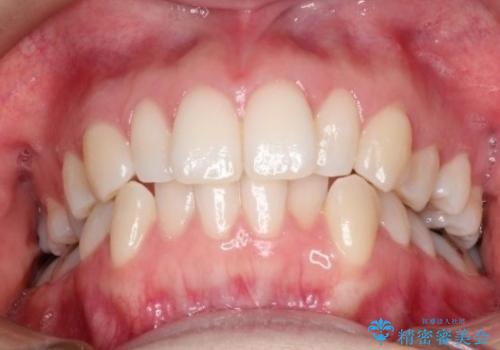

初診時の歯並びの状態としては、上下ともに前歯部の中等度のがたつきがあり、特に左上の前歯が1本内側に入り込んでしまっている状態でした。

また、2mm程度の正中離開がありました。

抜歯なし/インビザラインによるマウスピース矯正にて治療を行いました。